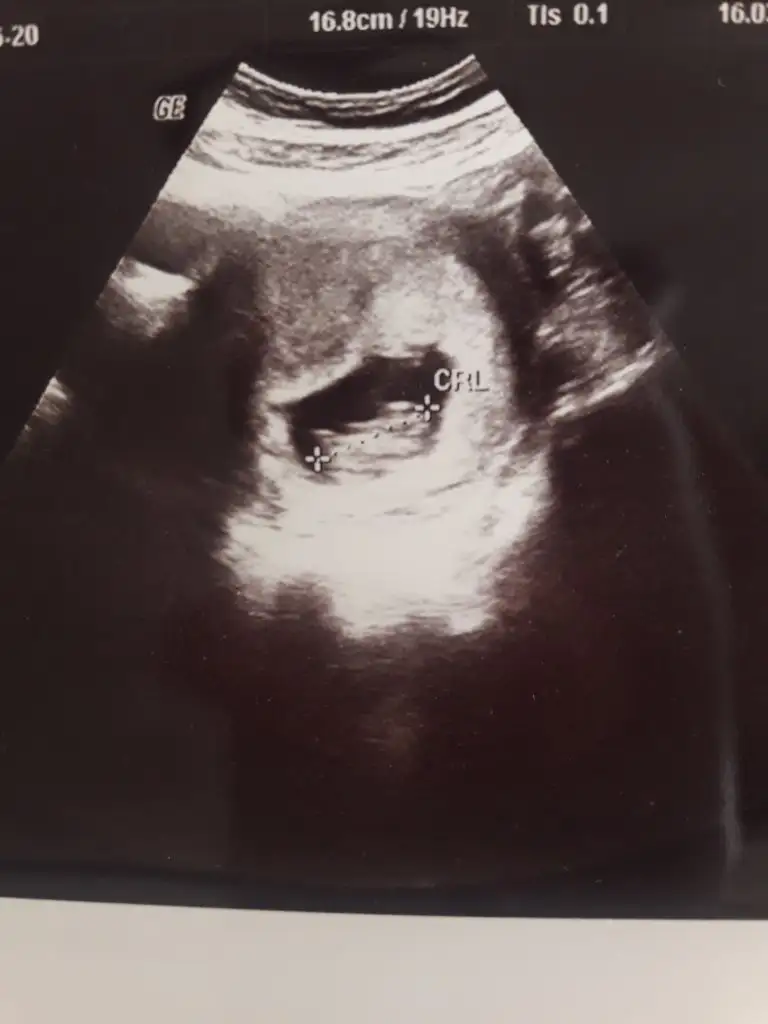

kız gibi duruyor canımKuzum buna bakabilir misin pekii 9 haftalıktı karından

5 ve 14. haftaya kadar olan ultrason fotolarınızı paylaşın. Vajinadan mı yoksa karından mı çekildiğini ve kaç haftalık olduğunu da mutlaka belirtin.